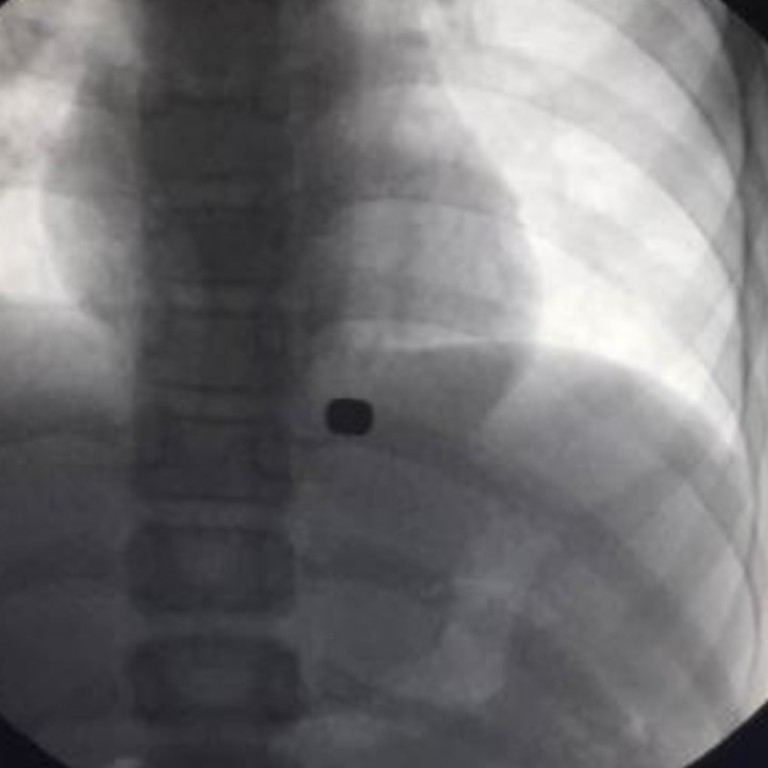

Hu and his team had tried to remove the button-sized magnets using an endoscopy, which is usually used to conduct internal examinations, but they found they were covered by tissues at the bottom of the boy’s stomach.

However. by attaching the powerful magnet to the endoscopy they were able to get round the problem.

Hu told the newspaper that without the magnets doctors would have had to dig a hole in the boy’s stomach.

“Even with open-chest surgery, it would be hard to find the magnets without tearing the tissue apart.”